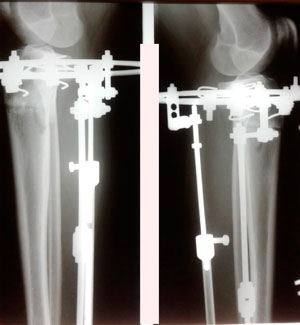

Дата операции - 12.09.2019г.

Дата снятия аппаратов - 06.12.2019г.

Срок сращения - 84 дня.